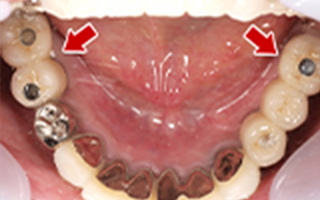

Before

After

| 68歳 男性 | 紹介 |

|---|---|

| 主訴 | れ歯が合わない 食べにくい 人生を豊かにしたい |

| 処置内容 |

上顎4本で12歯(オールオン4)、下顎4本5歯 上下抜歯即時埋入、即時荷重(手術当日にインプラントの上に仮歯装着) |

| 治療費用 | 上顎: 約220万(税込) 下顎: 約180万円(税込) |

| 治療期間 | 上顎: 9ヶ月 下顎: 6ヶ月 |

| リスク |

術後の腫れ、痛み(ピークは3日後、1週間で軽減) 上部構造物、仮歯の破折、人工歯根脱落リスクがあります |